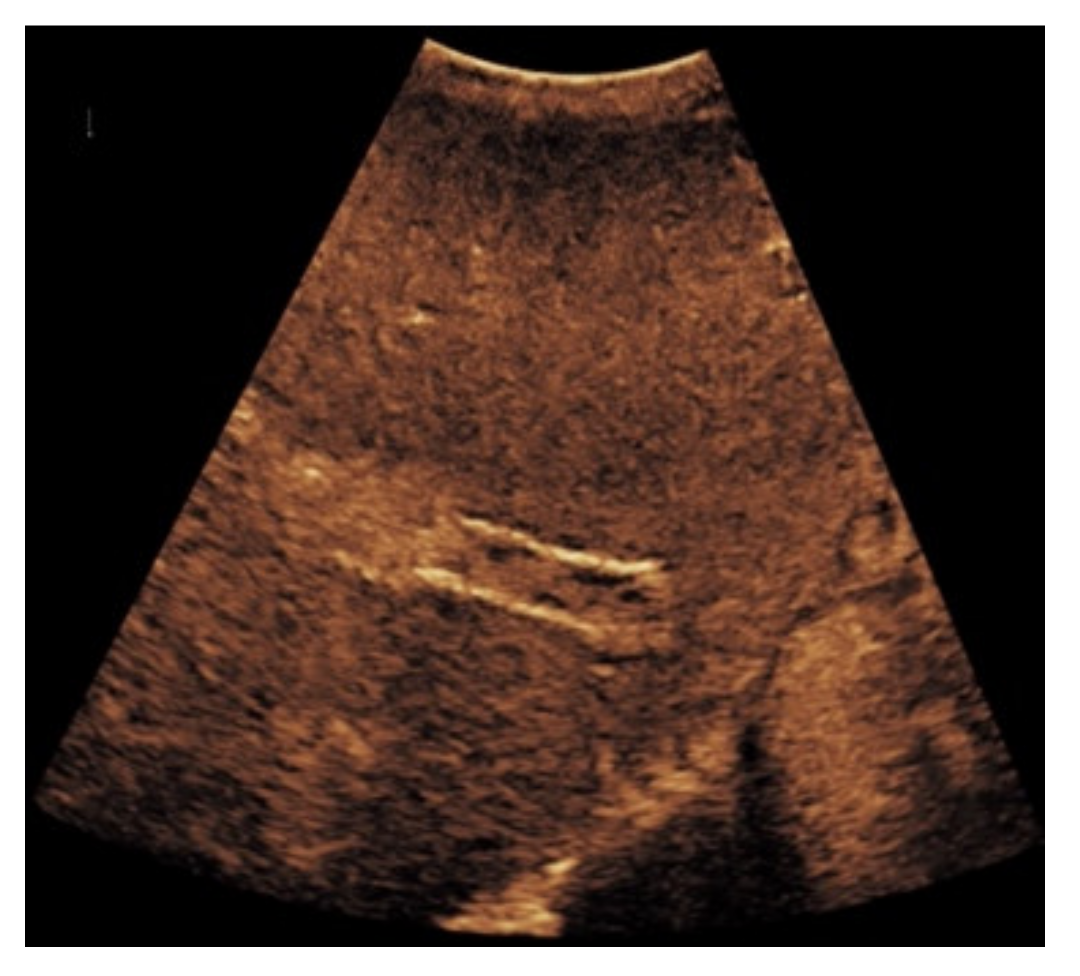

Figure 6. Same patient as in Figure 3. Contrast-enhanced ultrasound shows partial flow signal within the transjugular intrahepatic portosystemic shunt with marginal hypoechoic areas within the stent indicating thrombotic depositions.

When taking a closer look at the results of the CEUS examinations, 70.8% (n = 75) of the patients showed regular stent perfusion (Figure 4), 17.9% (n = 19) of the patients featured TIPS occlusion (Figure 5) while 6.6% (n = 7) patients had stent thrombosis (Figure 6). In contrast to the results from CDUS, there were no patients with only partial accessibility of the TIPS during CEUS, while the two patients with meteorism also were not assessable during CEUS. The three patients categorized in “others” showed simultaneous findings between CDUS and CEUS (Table 2).